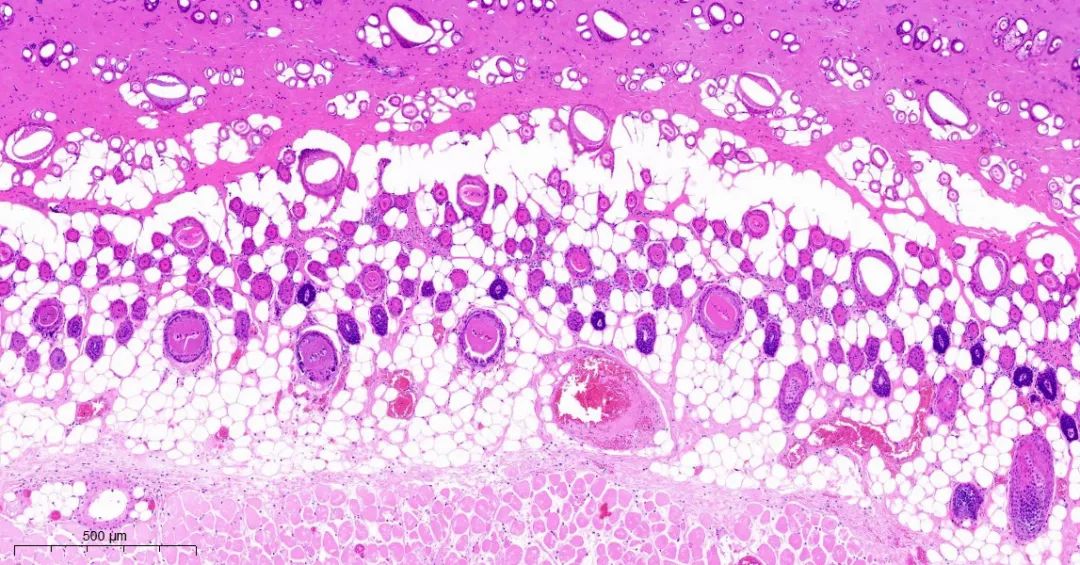

取正常对照组及模型组大鼠背部皮肤标本,常规固定,石蜡切片,HE染色,观察皮肤组织学变化。

模型2组皮组织切片对比